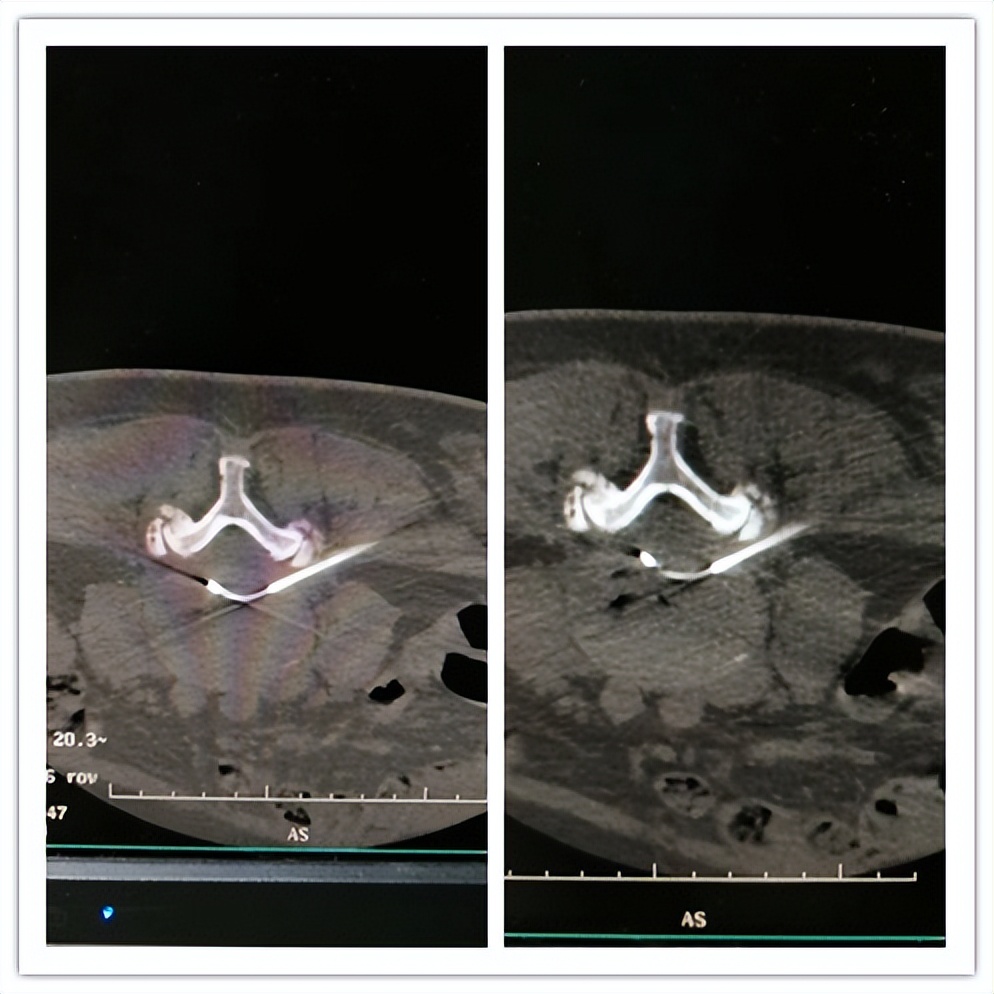

(腰椎间盘突出症:腰椎间盘射频热凝+臭氧消融)

(腰椎间盘突出症:腰椎间盘等离子)